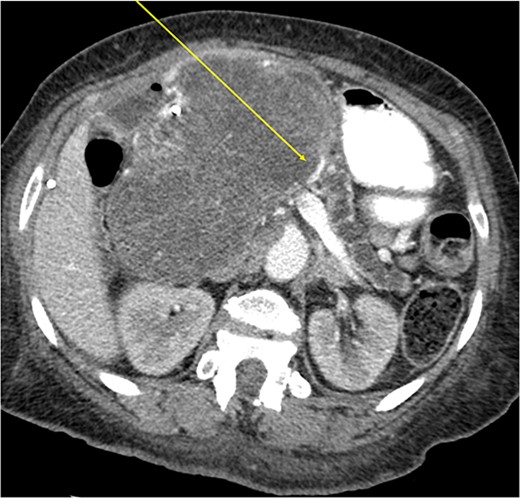

The mass extended up into the base of the liver, effaced the portal and superior mesenteric veins (SMV) (Fig. 4), and displaced the hepatic and superior mesenteric arteries.